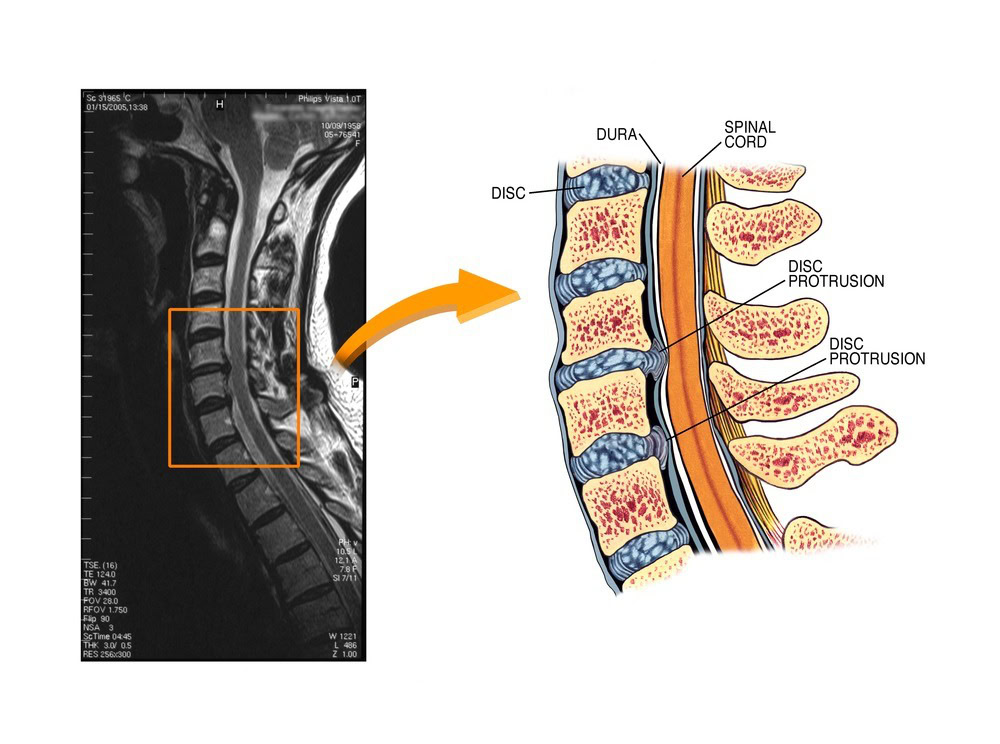

허리 디스크나 척추관 협착증이 있을 때 가장 대표적으로 시행되는 척추 주사입니다. 척추신경 바깥에 약물을 투여합니다.

신경근 차단술

특정 척추 신경 뿌리(신경근)가 눌려 통증이 발생할 때, 영상 장치로 보면서 해당 신경에 직접 약물을 주입하는 방법입니다.

- 허리/목 디스크

- 척추관 협착증